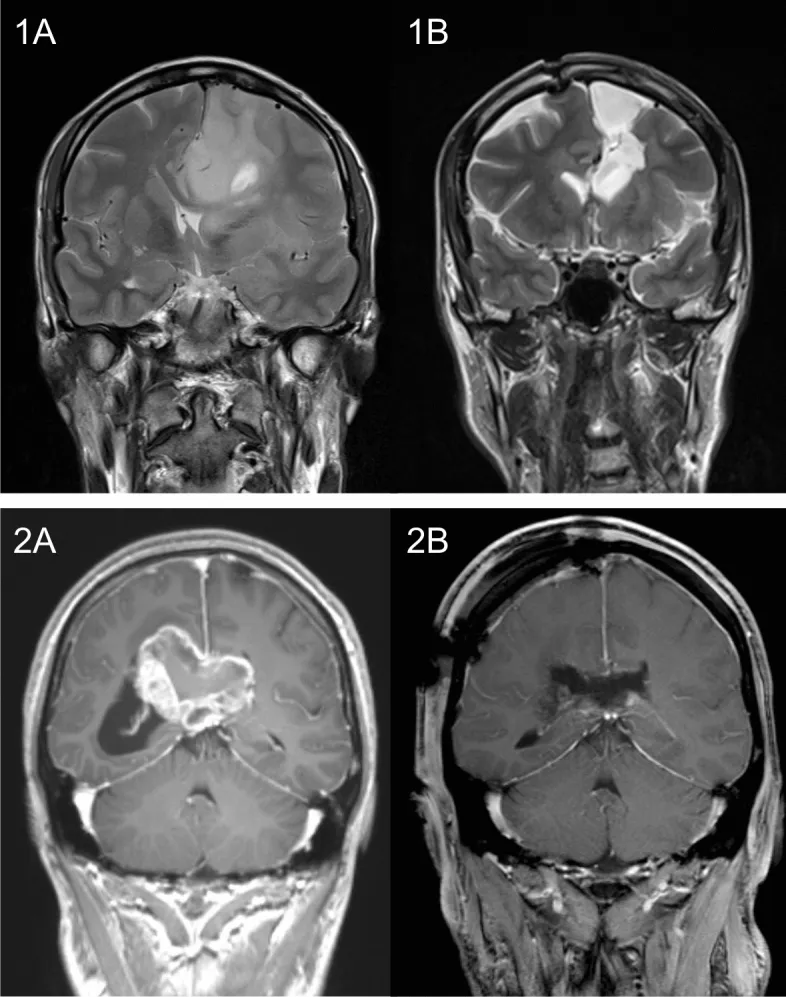

两例胼胝体侵犯性胶质母细胞瘤患者示例。图(1A)与(2A)显示术前肿瘤情况,图(1B)与(2B)显示术后结果。患者1,36岁,接受了巨大左额叶胶质母细胞瘤的次全切除术,后续行同步放化疗。该患者在任一观察时间点(即术前及长期随访期间)均未出现任何严重认知功能障碍。患者2,38岁,接受了侵犯胼胝体压部主体的巨大胶质母细胞瘤次全切除术。术前该患者存在严重记忆障碍,术后逐渐改善;术后新出现的轻度注意力及语言功能障碍亦随恢复逐步好转。